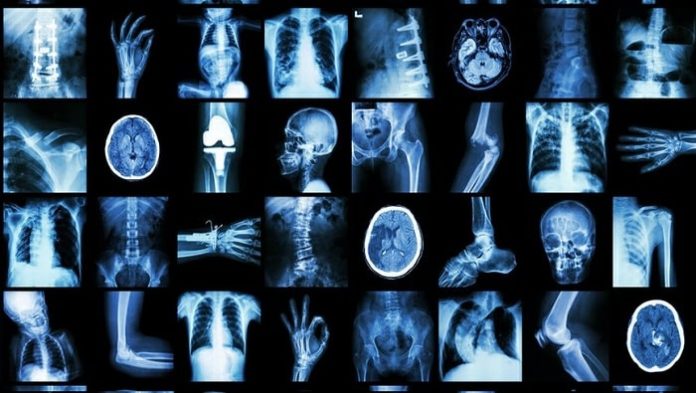

Zegami, the Oxford University data visualization spin-out, has announced it has written to the health ministers of ten countries asking them to provide X-rays of COVID-19 infected lungs. A diverse set of example images are needed in order to build a more robust machine learning model, a form of artificial intelligence, to assist health professionals identify cases of COVID-19. The use of artificial intelligence like this has the potential to provide better outcomes for patients and even lead to more effective treatments, if it can become fully operational.

To date, Zegami has access to 226 X-rays of COVID-19 infected lungs but needs around 10,000. Zegami, which is offering its services for free in the fight against coronavirus, says its new model could not only help identify and differentiate COVID-19 cases more easily from other lung conditions such as bacterial pneumonia and viral pneumonia, it could also help predict potential outcomes for patients by comparing their COVID-19 lung X-rays with other previous patients who had similar conditions, and what eventually happened to them based on different treatment options.

In developing its new platform, Zegami has initially used images of COVID-19 X-rays from the GitHub data initiative, which was launched by Joseph Paul Cohen, a Postdoctoral Fellow from Mila, University of Montreal. He is looking to develop the worldโs largest collection of X-ray and CT images of COVID-19 infected lungs, to enable automated diagnosis faster and more accurately.